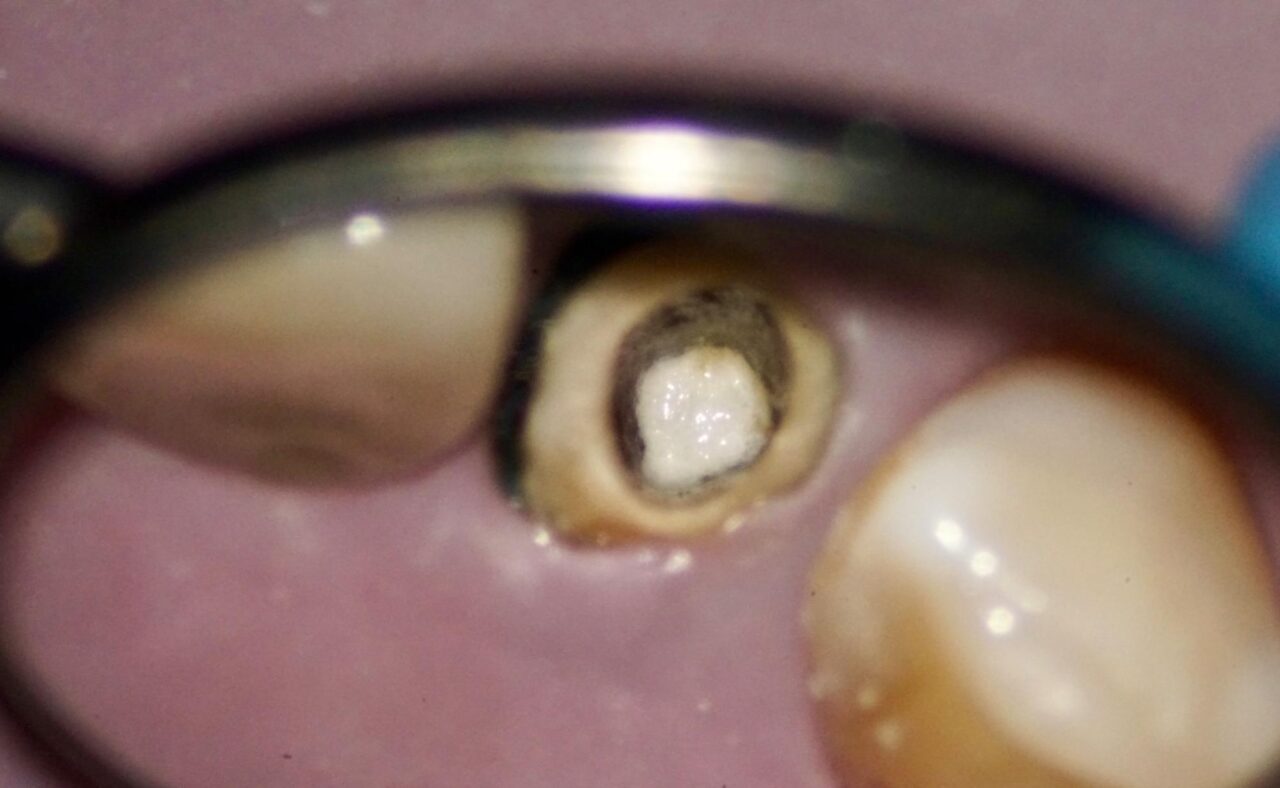

以前の根管充填材は、感染部質なので完全に取り除く必要があります。この写真では根尖部にまだ残っている事が確認できます。

根管内、根尖部がきれいになったと思われるので、根管洗浄を6%次亜塩素酸を満たした状態で根管内にレザーを用いて活性化させて細かいとことまで洗浄を行います。

根管内がきれいになっている事が、確認できます。